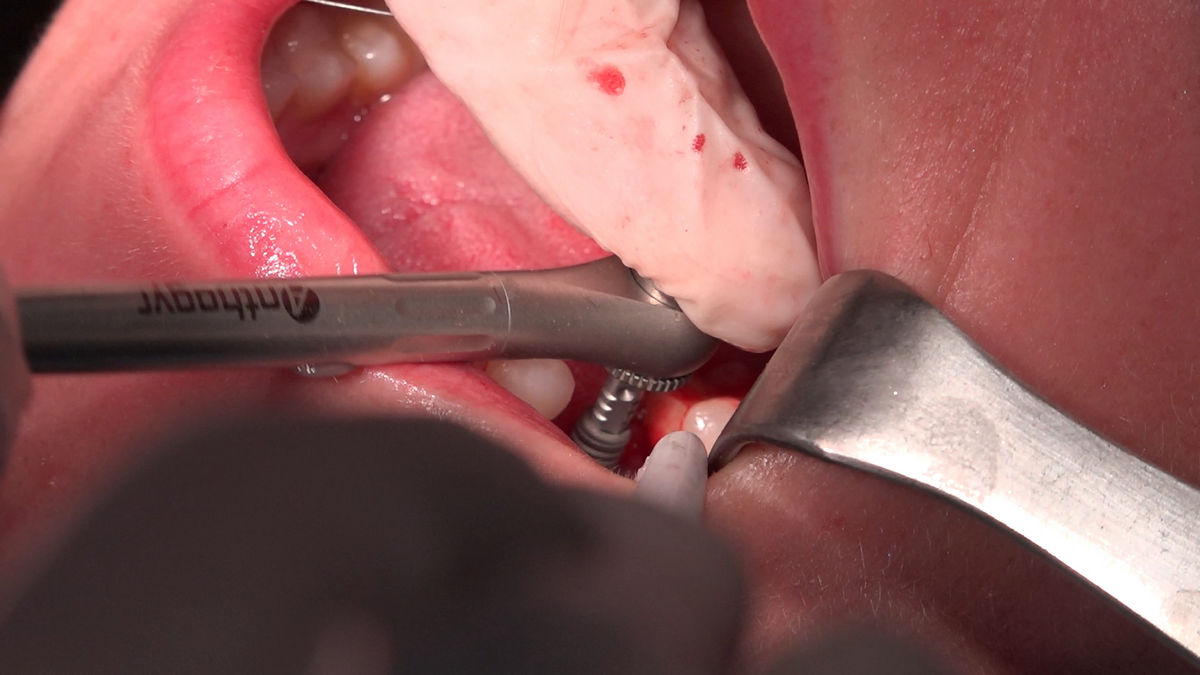

Chirurgia implantologiczna to temat wiodący 5 Sesji X Sezonu Practiculum Implantologii, która się odbyła 23-24 października 2020 roku. Bierze w nim udział 16 adeptów implantologii stomatologicznej. Zabiegi z udziałem Pacjentów jak zwykle poprzedziło omówienie i planowanie, tym bardziej, że zgodnie z planem wykonana została implantacja z wykorzystaniem szablonu chirurgicznego, który przygotowało laboratorium dentystyczne Wiligała Lab. Kursanci wykonywali szereg zabiegów implantologicznych i chirurgicznych oraz regeneracyjnych z zastosowaniem PRF, w tym sinus lift. Przeprowadzali je pod kierunkiem Lidera Umiejętności Implantologicznych dr n.med. Violetty Szycik, która wysoko oceniła wykonanie zabiegów.